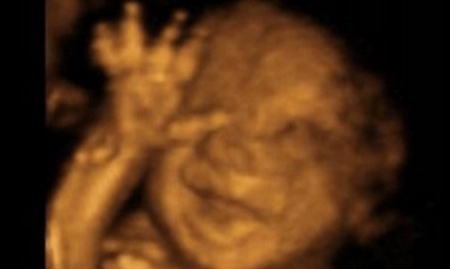

Professor Stuart Campbell, an eminent obstetrician whose 3D scan images of babies "walking in the womb" have fuelled the debate over late abortions, said: "It is a distressing situation when these babies are being born alive.